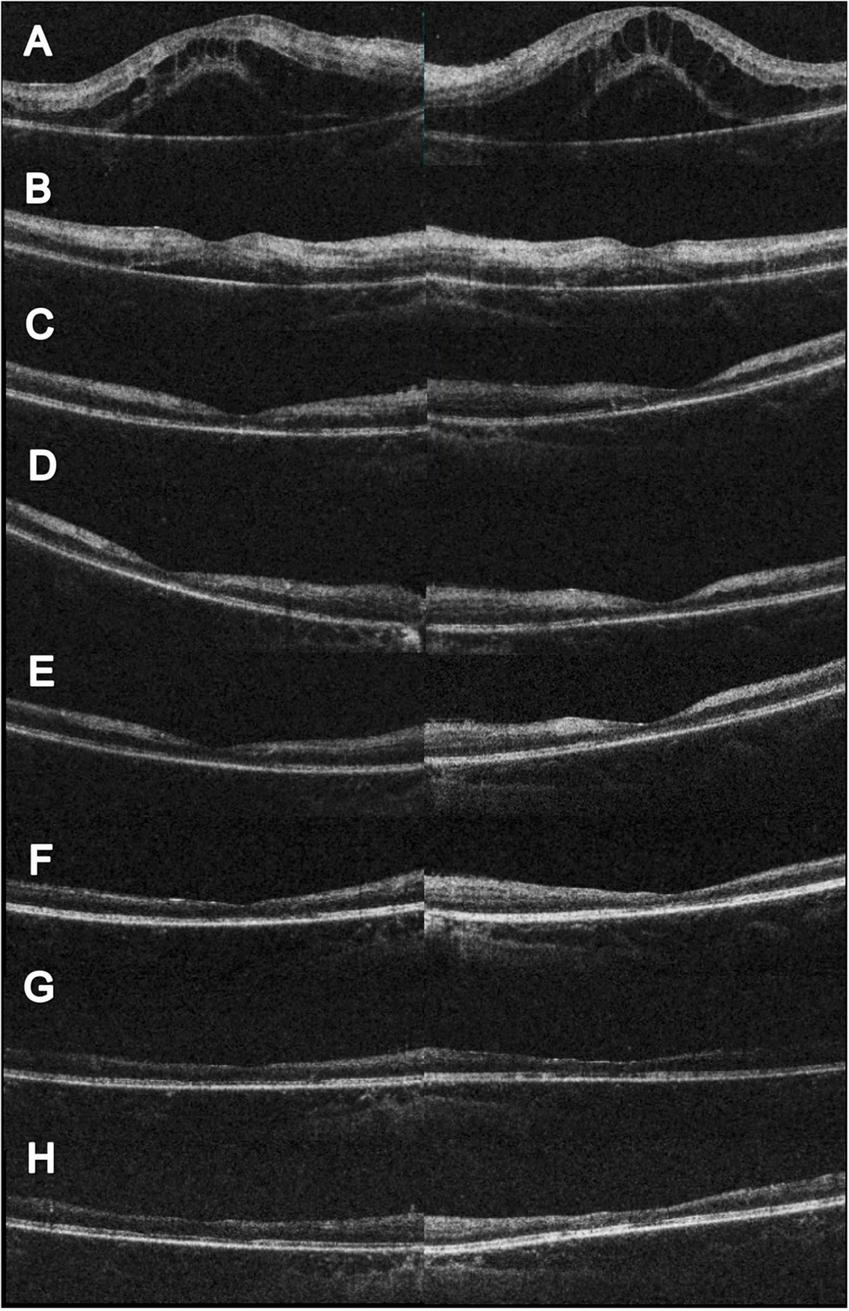

FIGURE 2

Serial changes in OCT. (A) Initial OCT showed profound macular edema with combine intraretinal and subretinal fluid. (B) Two weeks after initial visit, partial resolution of the macular edema; however, hyperreflective change could be noted at the inner and middle retinal layers. The visual acuity was 0.1 (right) and 0.05 (left). (C) Eleven weeks after initial visit, complete resolution of the macular edema. CFT 156 μm (right) and 147 μm (left). The visual acuity was 0.05 (right) and counting finger 30 cm (left). (D) Seventeen weeks after initial visit and 4 weeks following HBOT. Slightly reduce hyperreflectivity at the left eye could be noted. The visual acuity was 0.1 (both). (E) Twenty-one weeks after initial visit and 8 weeks following HBOT. Extensive retinal thinning with ellipsoid zone loss was noted. The visual acuity was 0.16 (both). (F) Twenty-eight weeks after initial visit and 15 weeks following HBOT. Reduced inner retinal thinning was noted. The visual acuity was 0.16 (right) and 0.2 (left). (G) Forty-three weeks after initial visit and 30 weeks following HBOT. Reduced inner retinal thinning was noted. The visual acuity was 0.05 (right) and 0.16 (left). (H) Sixty weeks after initial visit and 47 weeks following HBOT. Reduced inner retinal thinning was noted. The visual acuity was 0.1 (right) and 0.16 (left).

Although the bilateral FBA and macular edema gradually alleviated (Figures 1C, 2B) after several weeks of medical treatment, the BCVA improvement was minimal (0.05, right eye; counting finger, left eye) (Table 1). Persistent macular ischemia, with clinical presentations of profound PuR and compatible ischemic hyperreflective changes on OCT (Figures 1C, 2C), was identified to be the main cause of poor vision. Therefore, HBOT was initiated with 2.0 atmosphere absolute (ATA) for 75 min per session, 1 session per day, 5 days per week. After a total of 39 sessions of HBOT, the visual acuity steadily improved to 0.16 (RE) and 0.2 (LE), with gradual resolution of Purtscher fleckens (Table 1). Subsequent immunosuppressive medications, including methotrexate (10 mg/week) and cyclosporine (50 mg/day), were also initiated for FBA treatment and corticosteroid tapering (Figure 3). Follow-up fundus photograph and fluorescein angiography performed 21 weeks after the initial visit and 8 weeks following HBOT revealed almost completely resolution of FBA and decrease in size of PuR, but extensive macular and mid-peripheral retinal ischemia (Figures 1D, E). Therefore, retinal photocoagulation on the non-perfusion area was performed 13 weeks after the initiation of HBOT to prevent further neovascular complications, such as vitreous hemorrhage, tractional retinal detachment, and neovascular glaucoma (Figure 1F).

The visual prognosis of FBA is excellent. However, similar to our case, a minority (10%) may present with poor final visual acuity (<0.1) due to structural complications such as macular pathologies, optic atrophy, and retinal vascular occlusions (1). Kwon et al. (10) reported a 39-year-old male with an unusual case of unilateral FBA associated with Behçet’s disease. Neovascularization of the disc was found, despite panretinal photocoagulation for non-perfusion areas. Foveal atrophy and disruption of the photoreceptor layer in the macular area developed with final vision limited to hand movement, 8 months later (10). In our patient, although initial macular edema responded favorably to treatment, macular ischemia with PuR was refractory to combined anti-inflammatory and antiplatelet therapy. Follow-up fluorescein angiography revealed extensive arterial and capillary dropout, and further neovascular complications, such as vitreous hemorrhage, retinal vascular occlusion, iris rubeosis, and neovascular glaucoma require close monitoring (7). As most ophthalmological treatment modalities, such as intravitreal anti-VEGF injections and panretinal photocoagulation, are only capable of suppressing VEGF release and avoiding further neovascular complications, few options are available to rescue retinal perfusion in such challenging scenarios. Therefore, HBOT is a viable option for physicians. As the patient had received numerous medications, it was not possible to evaluate the sole effect of HBOT. However, considering the significant structural changes in macular ischemia and foveal thinning on follow-up images (Figures 1C–F, 2D–H), the salvage effect of HBOT may have played a role in the visual recovery process.